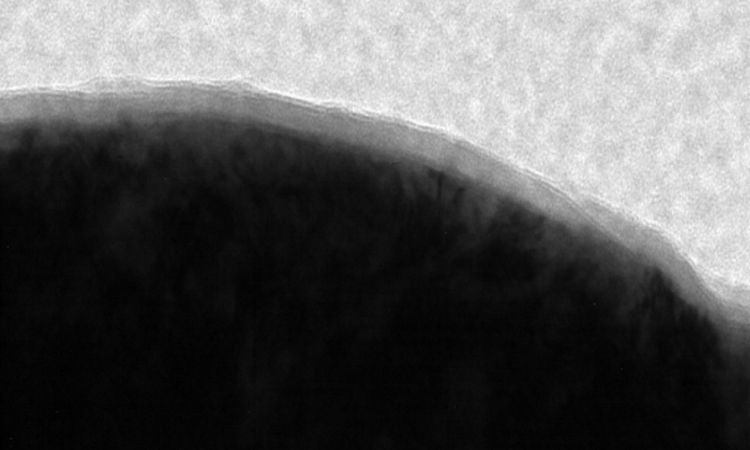

显微 CT 技术在牙科领域的应用领域涵盖了组织工程、用于有限元分析的真实数据识别、确定牙齿中的矿物质浓度,以及人类学研究中牙釉质厚度、颅面骨结构和发育的测量,同时也应用于牙髓研究,用于评估种植体和周围骨(见下图)。显微 CT 为牙髓研究提供了巨大便利,尤其是在识别牙根管形态、检查根管准备情况、评估填充物,并能在治疗后进行检查方面发挥着重要作用。